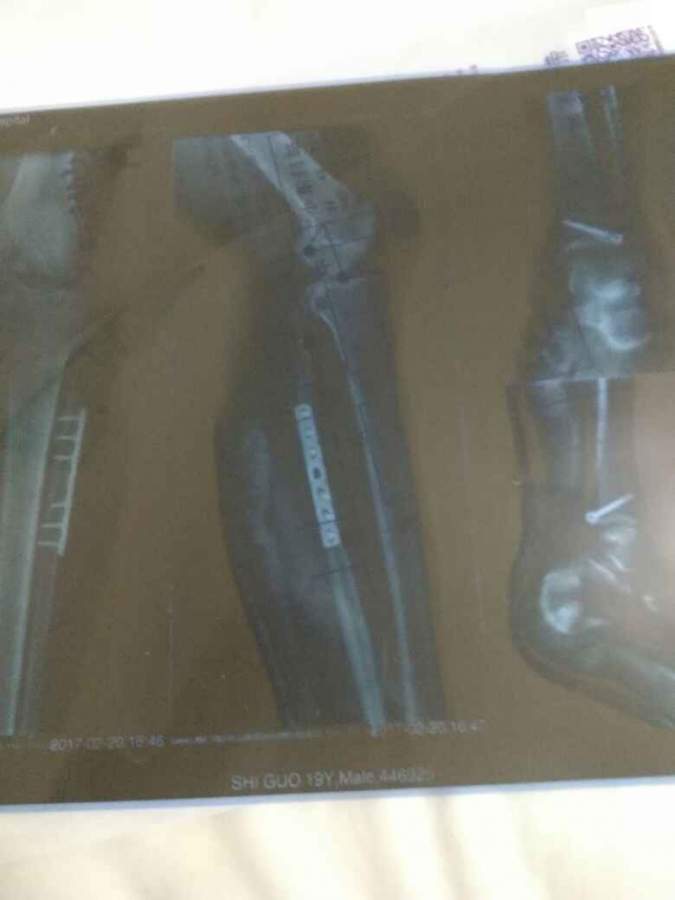

ÎҵĽÅ×óõ׹ǺÍ×óëè¹Ç¹ÇÕÛ×óõ×Èý½ÇÈÍ´ø¶ÏÁÑ£¬ÏÖÕýÔÚ²¿¶Ó£¬ÏëÎÊ´óÉñÃÇÕâÑùµÄÉ˶à¾Ã²ÅÄÜÑøºÃ£¬ÔÚ²¿¶ÓÄÜÆÀ²ÐÂð @wangyc3 @carci ·¢×ÔСľ³æAndroid¿Í»§¶Ë |

ÒÔǰÎÒÒ²ÊÇ×ó½Åõ׺Í×öëè¹Ç¹ÇÕÛ£¬ÊÖÊõÖ®ºó´óÔ¼Èý¸öÔ²ÅÄÜÃãÇ¿×ß·µÄ ·¢×ÔСľ³æAndroid¿Í»§¶Ë |